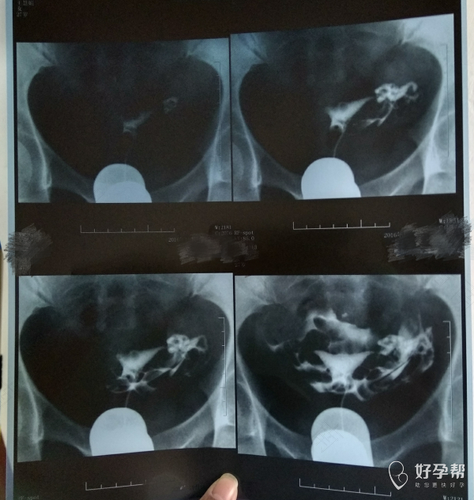

输卵管造影手术是指造影剂注入子宫腔内,经子宫腔传送到输卵管内,以了解子宫腔和输卵管是否处于通畅的状态。当女性输卵通不通或者通而不畅时,会影响到女性的受孕机率,所以及时的进行诊断治疗是很有必要的。那么什么时候需要做输卵管造影?

一般女性在备孕两年仍未成功受孕或者出现了宫外孕,是需要检查输卵管是否处于通畅的状态,此时需要做输卵管造影。输卵管造影一般在月经干净后的3到7天进行,在检查期间要禁止性生活,避免盆浴。它通过显像来确认女性的输卵管是否正常,如果出现异常,可以采用输卵管再通技术来保证女性正常孕育生命的能力。